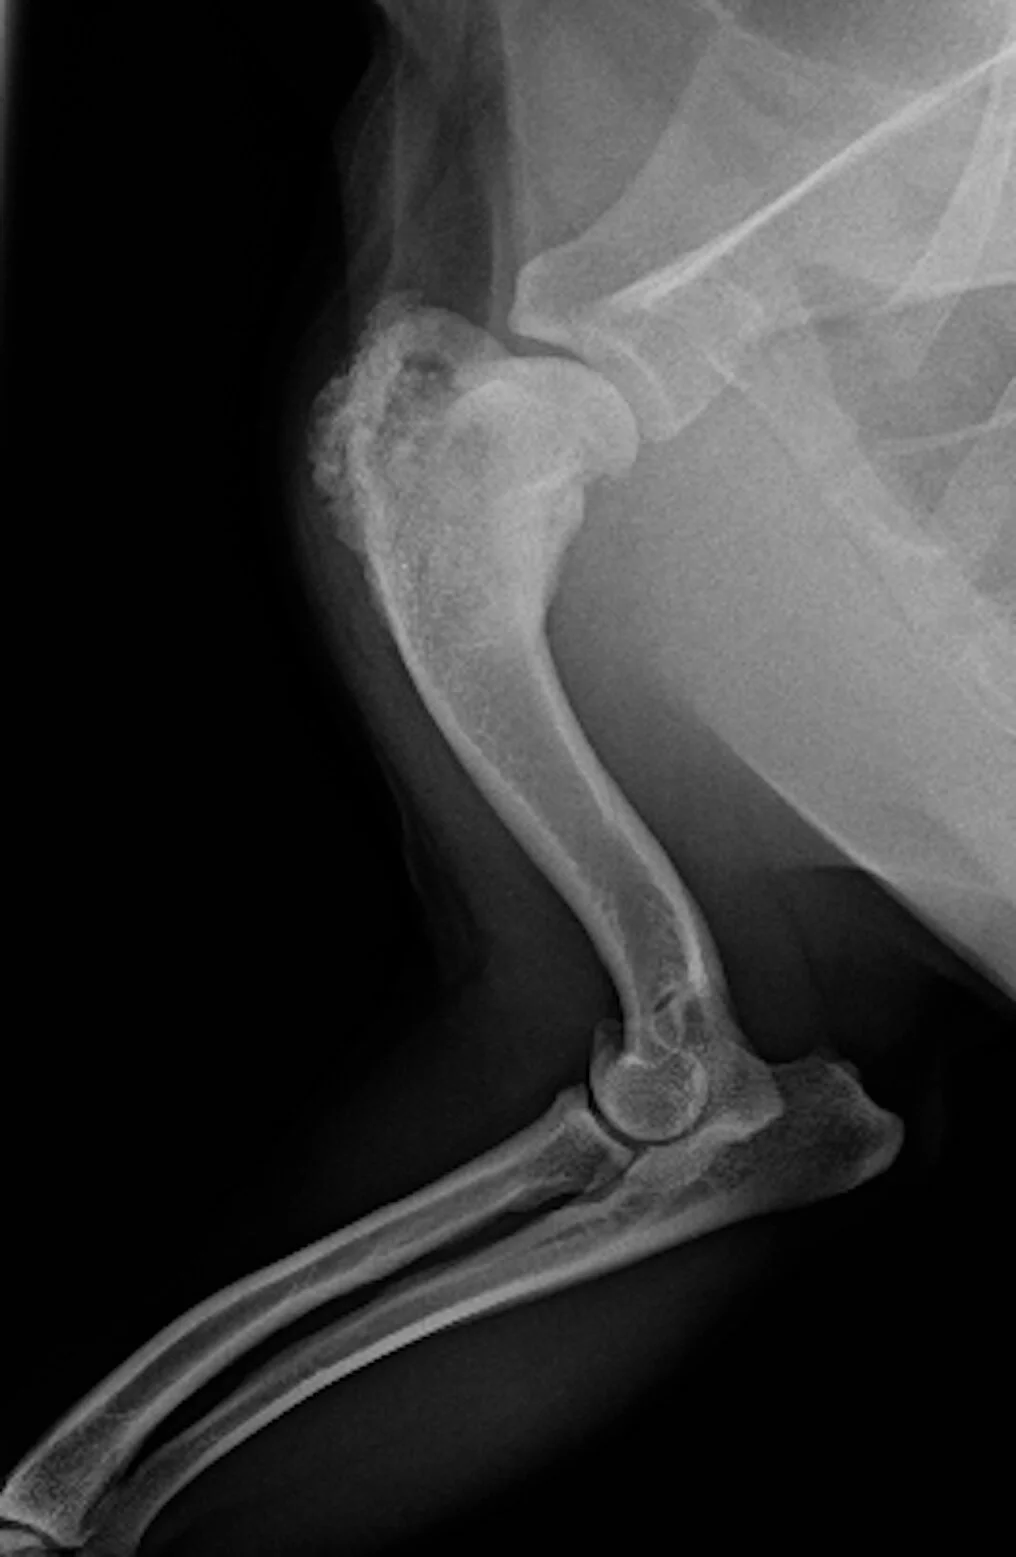

Bone Pain Osteosarcoma Dogs / A Dog In The Cancer Fight Comparative Oncology In Osteosarcoma Intechopen - Bones may be affected by tumors and most frequently these are localized close to the knee joint or below the the dog with bone cancer will be in a lot of pain and relieving this pain is a top priority to comfort your pet.. Signs of osteosarcoma in dogs may include: A dog with osteosarcoma will easily break a bone while jumping or running and this can be an extremely painful condition. While the prognosis can be discouraging to say the least, there are options osteosarcoma is an aggressive malignant tumor that initially develops within the bone. It is a malignant tumour, meaning it is a very painful cancer and unfortunately the prognosis is quite poor. This is an osteosarcoma, the most common bone cancer in dogs.

A Dog In The Cancer Fight Comparative Oncology In Osteosarcoma Intechopen from www.intechopen.com In general, osteosarcoma has a terrible outlook. In this tumor, the cancerous cells. This is an osteosarcoma, the most common bone cancer in dogs. This is typically later on in the disease however. Read on for information on the symptoms, causes, and conventional treatment of dog bone cancer. Osteosarcoma can occur in any bone in a pet's body, but in dogs, most tumors appear in the front limbs near the shoulder, wrist, and knee. Treatment of osteosarcoma in dogs. The disease develops deep within the bone.

Bone lesions—skull, ribs, pelvis, femur, humerus, sternum, spinal cord osteosarcoma: Osteosarcoma can cause knee pain or pain and swelling in the affected area. Some inherited bone conditions can raise the risk of osteosarcoma. In some cases, dogs with bone cancer develop anorexia and decline endurance. Typically, osteosarcoma affects larger breeds and. Osteosarcoma in dogs can grow inside of any of their bones, but it is most often seen in the wrist how common is dog osteosarcoma? Osteosarcomas are aggressive tumours that spread to other parts of the body (often the lungs). Osteosarcoma is an aggressive cancer that can develop in any bone of the body but the majority is seen in the limbs. Osteosarcoma refers to the most common bone tumor found in dogs. A dog with osteosarcoma will easily break a bone while jumping or running and this can be an extremely painful condition. Osteosarcoma in dogs is cancer of bones/ tumor in bones and it affects a large breed of dogs. In general, osteosarcoma has a terrible outlook. The cancer tends to form at or near the growth plates.

Canine Bone Cancer The Big Story On Osteosarcoma Orvis from assets.orvis.com While the prognosis can be discouraging to say the least, there are options osteosarcoma is an aggressive malignant tumor that initially develops within the bone. The front limbs are most commonly affected, according to vet cancer specialists. Osteosarcoma, the most common type of bone cancer, often starts in the long bones — the legs or the arms — but it can occur in any bone. They are most common in leg bones, but can affect any bone in the body. With pain relief alone, most dogs can only expect to live for 1. Osteosarcoma is the most common form of bone cancer. Osteosarcoma can occur in any bone in a pet's body, but in dogs, most tumors appear in the front limbs near the shoulder, wrist, and knee. Osteosarcoma is extremely aggressive, and it spreads quickly to other parts of the body, making early detection and.

Sadly, the outlook for a dog with an. Read on for information on the symptoms, causes, and conventional treatment of dog bone cancer. Signs of osteosarcoma in dogs. Does my dog have osteosarcoma? Many dogs conceal their pain exceptionally well so you do. They can include swelling, lameness, and bone pain. In this tumor, the cancerous cells. In some cases, dogs with bone cancer develop anorexia and decline endurance. B one cancer in dogs can cause lameness, swelling, and intense pain. Osteosarcoma can occur in any bone in a pet's body, but in dogs, most tumors appear in the front limbs near the shoulder, wrist, and knee. Veterinarians often use the phrase away from the elbows & toward the knees to remember the. The front limbs are most commonly affected, according to vet cancer specialists. Osteosarcoma or bone cancer is mostly appendicular i.e.

Osteosarcoma in dogs is a primary bone tumour. B one cancer in dogs can cause lameness, swelling, and intense pain. Its main point of occurrence is the appendicular skeleton or the limbs and it weakens the affected bone from inside and makes movement extremely painful. Signs of osteosarcoma in dogs. As the tumor develops, the normal bones swell.

Osteosarcomas are aggressive tumours that spread to other parts of the body (often the lungs). Just because your pet can't rate it does not means it doesn't feel it. Pain progresses as the bone is destroyed from the inside out. Osteosarcoma is the most common bone tumor is dogs, accounting for 85% of all bone tumors. Some limb pain during growth is normal for active children and teenagers. It's a highly malignant and aggressive tumour, of which 75% is found in the legs of large and survival rates with bone cancer. In general, osteosarcoma has a terrible outlook. Osteosarcoma refers to the most common bone tumor found in dogs. Bone pain, tenderness (especially back, ribs; In osteosarcoma, the tumor originates from within the affected bone and destroys it from the inside out. It can be very painful as it grows from the inside out, destroying the. Affects the long bones (distal femur, proximal tibia, proximal humerus). Any of the symptoms above are not necessarily.